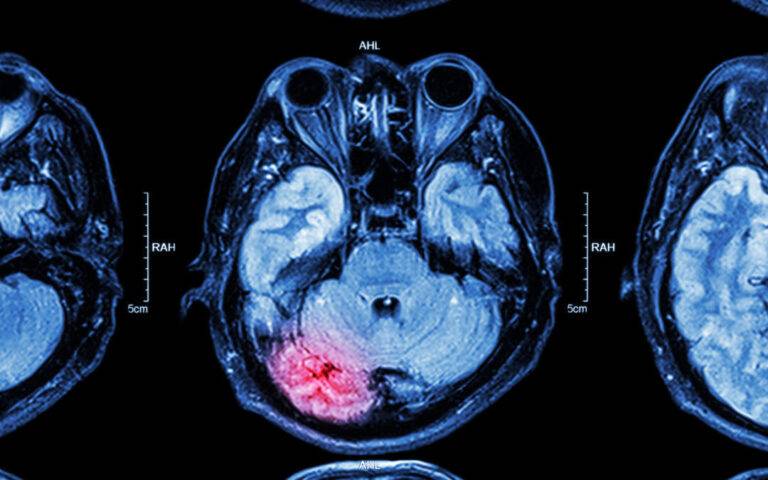

The imaging matters enormously in these cases. A standard CT scan in the emergency room may show the initial bleed but miss the contrecoup damage entirely. An MRI with diffusion tensor imaging is far more sensitive and can reveal the full extent of the axonal damage. If your ER visit only included a CT and you are still having symptoms weeks later, push for the MRI. The imaging findings are what separates a fifty-thousand-dollar settlement from a seven-figure case.

A coup contrecoup injury involves two impact points in the brain — the coup injury occurs at the site of initial impact, and the contrecoup injury occurs on the opposite side of the brain as it rebounds inside the skull. It happens when the head is struck with significant force or stops suddenly — car accidents, falls, assaults, and sports impacts are common causes. The result is damage to two separate brain regions simultaneously, which makes these injuries more complex and often more severe than single-impact TBI.

Standard CT scans frequently miss coup contrecoup injuries, especially in the acute phase. The damage occurs at the cellular level in many cases, which requires MRI or specialized neuroimaging to detect. Emergency rooms focus on life-threatening hemorrhage and may discharge a patient whose imaging looks "normal" despite significant brain injury. Symptoms — cognitive changes, personality shifts, memory problems, headaches — may emerge gradually over days or weeks. By the time the injury is fully understood, the connection to the accident may be challenged by insurance companies. I work with neurologists and neuropsychologists who understand these injuries.